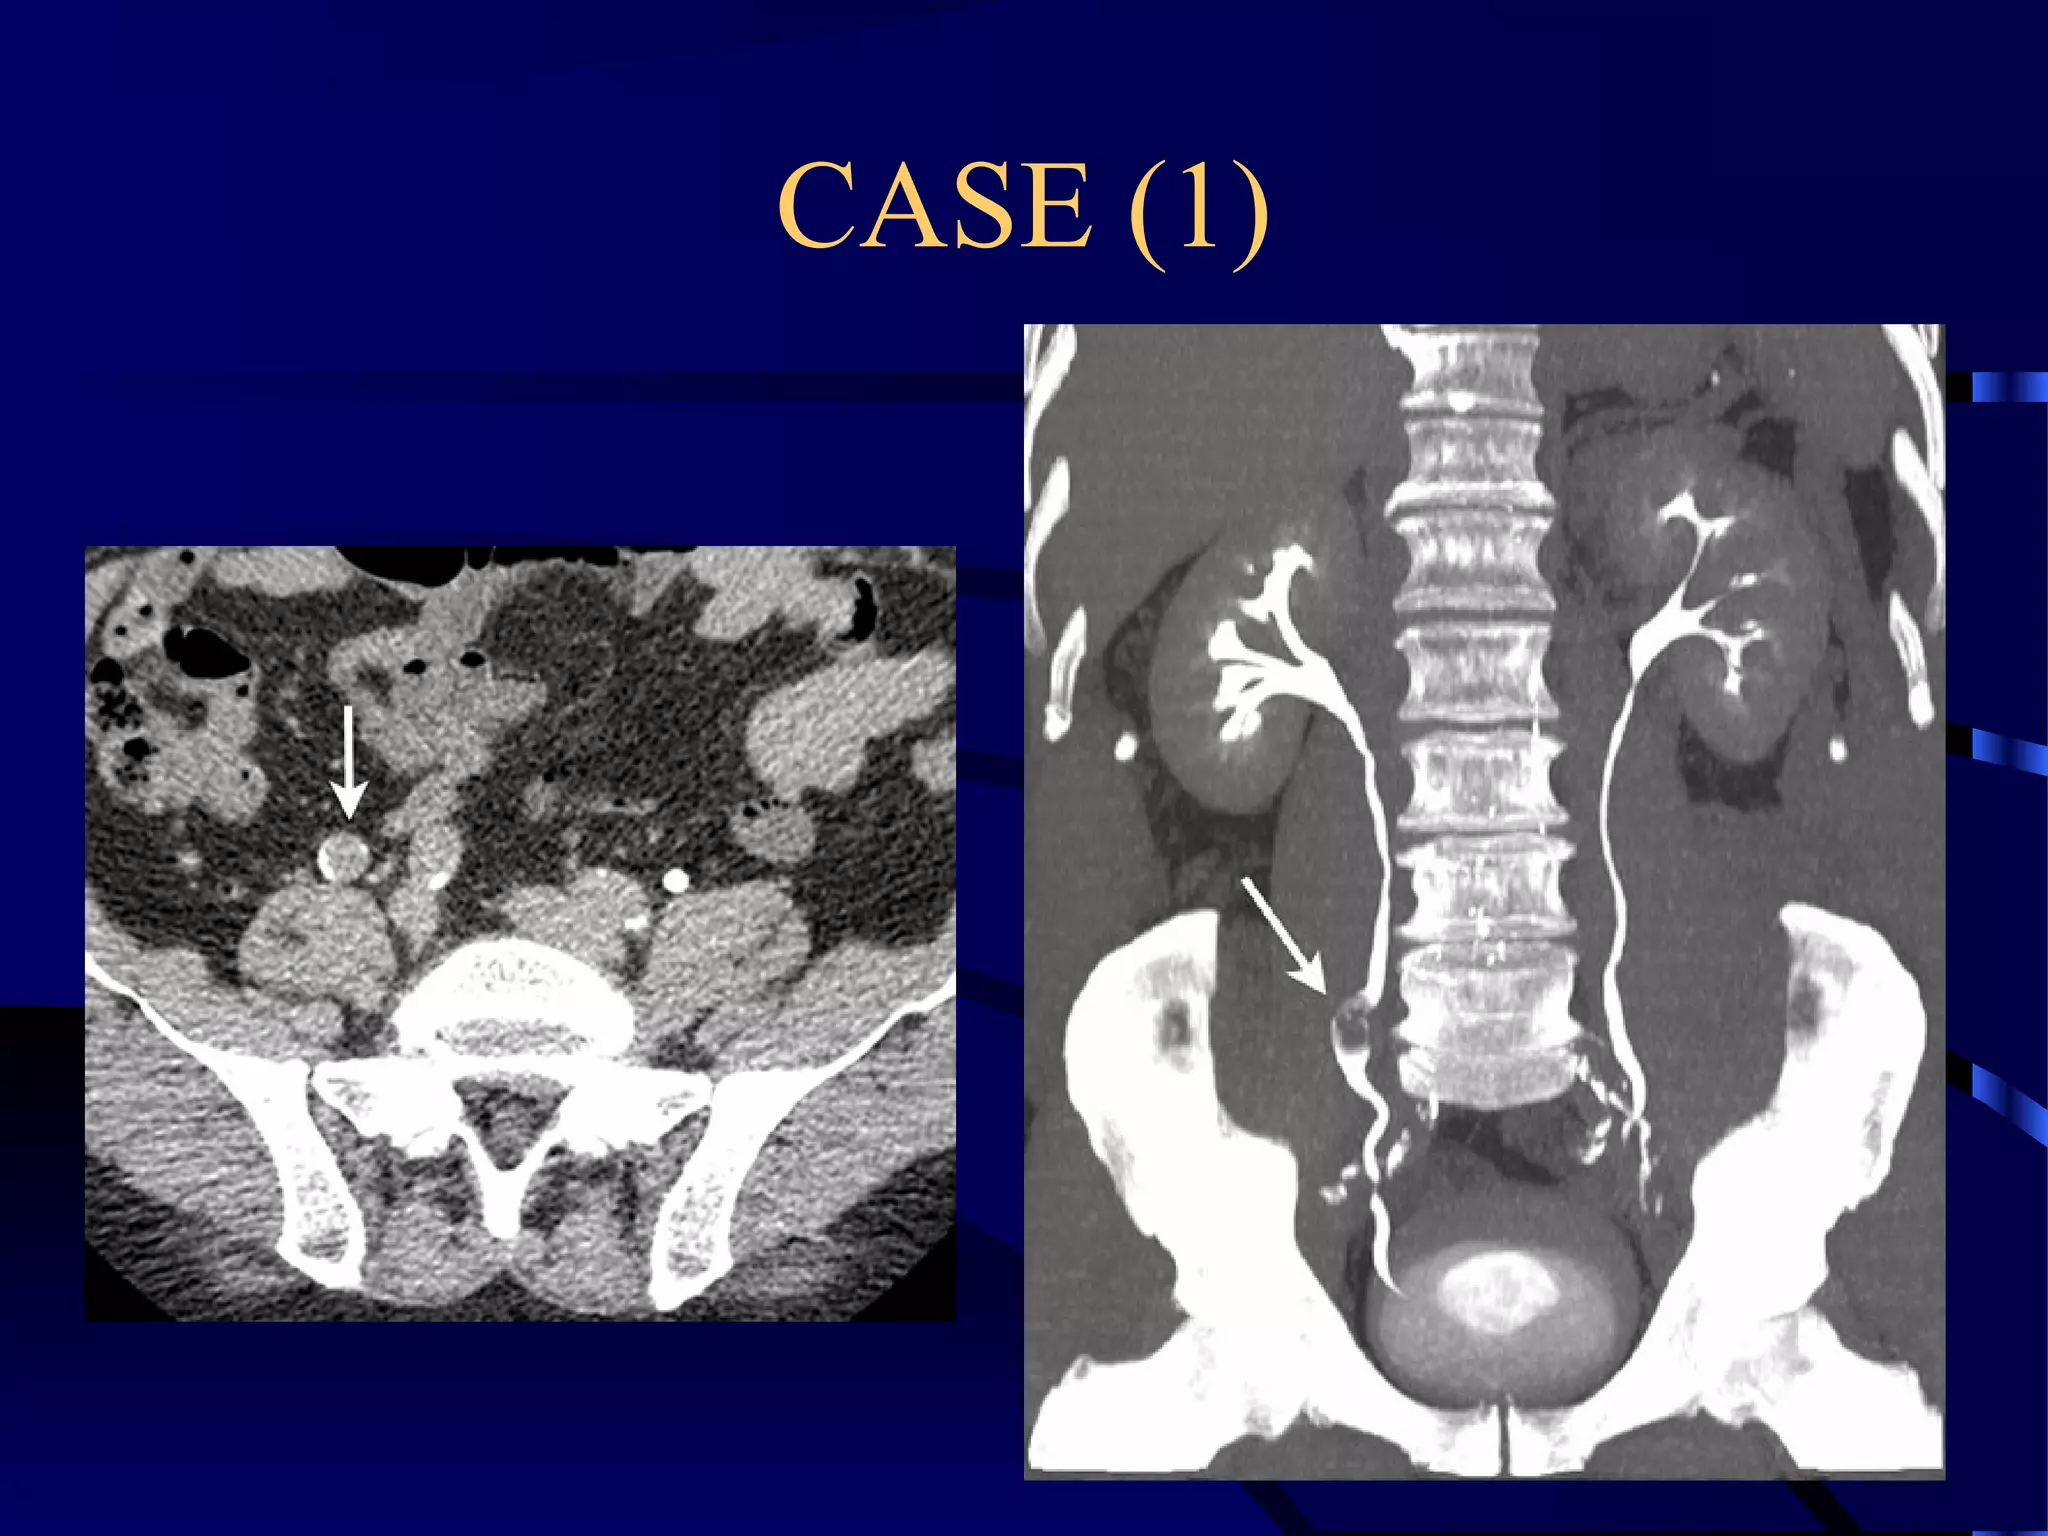

CASE (1)

NON ENHANCED CT SHOWING

BILATERAL RENAL PELVIS

CALCULI WITH MARKED

PYELITIS.

ENHANCED CT SHOWING

GOOD ENHANCEMENT.

MIP; THE STONES ARE WELL-SEEN WITHIN THE

OPACIFIED RENAL PELVIS.